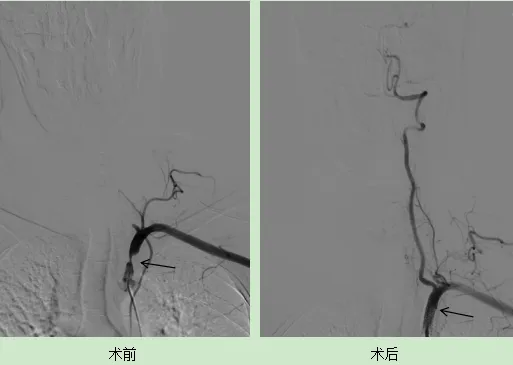

手術(shù)進(jìn)行順利,術(shù)后李大爺?shù)淖箧i骨下動脈狹窄得到顯著的改善,血管顯影效果良好,雙上肢血壓基本一致,李大爺頻繁發(fā)作的頭暈癥狀基本上消失了。在術(shù)后的第三天,李大爺便康復(fù)出院,重新回歸了正常的生活。 眩暈二科 滄州市中心醫(yī)院神經(jīng)內(nèi)科醫(yī)學(xué)中心眩暈二科是集醫(yī)療,預(yù)防,科研,教學(xué)全面發(fā)展的綜合性病區(qū),是一支經(jīng)驗(yàn)豐富,技術(shù)精湛,業(yè)務(wù)素質(zhì)強(qiáng),學(xué)術(shù)梯隊健全合理的專業(yè)技術(shù)隊伍。醫(yī)護(hù)人員共25人,其中副主任醫(yī)師5人、主治醫(yī)師4人、住院醫(yī)師3人,均為國內(nèi)知名高等醫(yī)學(xué)院校研究生畢業(yè),各級醫(yī)師均完成了北京宣武醫(yī)院,北京天壇醫(yī)院,北大醫(yī)院等知名醫(yī)院的進(jìn)修學(xué)習(xí)任務(wù)。 眩暈二科擁有國際先進(jìn)眩暈診療設(shè)備,如眼震視圖儀、視頻頭脈沖試驗(yàn)系統(tǒng)等,能夠精準(zhǔn)評估患者的前庭功能狀態(tài),對于常見的眩暈疾病,可以迅速診斷精準(zhǔn)治療,減少患者來往醫(yī)院次數(shù),節(jié)省費(fèi)用。對于復(fù)雜疑難的眩暈疾病,眩暈二科擁有整套成熟的診療機(jī)制,還可通過醫(yī)院多學(xué)科會診、北京各大醫(yī)院專家會診指導(dǎo),依據(jù)患者病情,制定個性化治療方案及康復(fù)計劃,并提供專業(yè)的康復(fù)指導(dǎo),通過前庭康復(fù)訓(xùn)練等手段,幫助患者恢復(fù)前庭功能,提高生活質(zhì)量。 科室診療范圍: 科室特色技術(shù)項目: 1、目前在眩暈診治方面有著鮮明的特色和傳統(tǒng)優(yōu)勢,科室內(nèi)醫(yī)務(wù)人員先后于北京天壇醫(yī)院眩暈中心,北京航天中心醫(yī)院師從國內(nèi)眩暈大咖對眩暈疾病的診療達(dá)到國際水平,同時本科室配備眼震電圖,視頻脈沖甩頭等先進(jìn)儀器,結(jié)合先進(jìn)理念及技術(shù)設(shè)備大大改善了眩暈患者的病痛, 提高了患者生活質(zhì)量。 2、急性后循環(huán)腦梗死早期,時間就是大腦,在卒中后“時間窗”內(nèi)完成靜脈溶栓治療或動脈取栓開通血管治療,是目前腦梗死診治的首先方法。明顯降低了腦卒中的致死率及致殘率。目前本科室腦血管狹窄的再通治療,動脈取栓治療等方面經(jīng)驗(yàn)豐富,術(shù)后效果顯著,得到廣大患者一致好評。 3、在前庭性偏頭痛,心因性眩暈方面有著豐富的臨床經(jīng)驗(yàn),結(jié)合先進(jìn)檢查手段,最新的治療方案,使患者早日得到明確的診斷及時治療,恢復(fù)健康。 前庭功能檢查室 副主任醫(yī)師,眩暈二科主任,碩士研究生,河北醫(yī)科大學(xué)碩士生導(dǎo)師。本科畢業(yè)于山東大學(xué)醫(yī)學(xué)院,從事神經(jīng)內(nèi)科臨床工作18年,擅長中樞性眩暈—后循環(huán)腦梗死,后顱窩腦出血,蛛網(wǎng)膜下腔出血、前庭性偏頭痛等疾病診治。外周性眩暈其中包括良性陣發(fā)性位置性眩暈、前庭神經(jīng)炎、梅尼埃病、突聾伴眩暈等疾病的診治與治療;心因性頭暈,其中包括心因性頭暈、持續(xù)姿勢性恐懼型頭暈(PPPD);頭暈狀態(tài)-暈厥發(fā)作有豐富的經(jīng)驗(yàn)。2014年于宣武醫(yī)院進(jìn)修1年。目前在研課題3項,發(fā)表論文10余篇,獲河北省衛(wèi)健委科研二等獎2項,滄州市科學(xué)進(jìn)步三等獎1項。 社會任職: 專業(yè)擅長: 各種中樞性、外周性、心因性眩暈,頭暈-暈厥發(fā)作等。